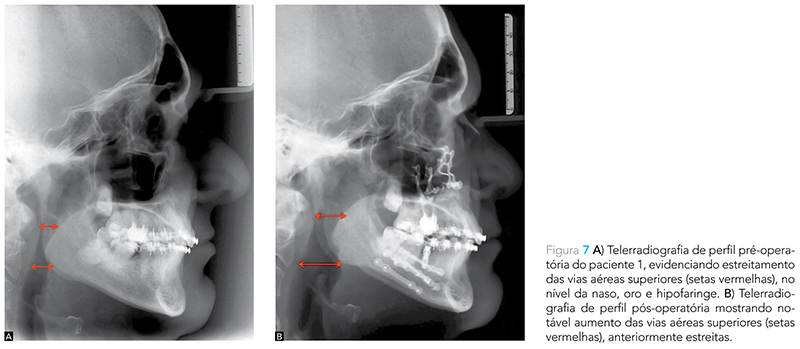

Os autores relataram, ainda, terem feito uso da técnica para o tratamento de ronco e SAOS nos quatro anos anteriores à publicação do artigo, obtendo sucesso clínico, tanto quando foi usada independentemente, como quando indicada em combinação com a cirurgia segmentada da maxila e/ou avanço cirúrgico mandibular. Eles não encontraram nenhum caso de insuficiência velofaríngea, fala hipernasal, estenose palatal, infecção ou comprometimento vascular dos segmentos ósseos32 (Fig. 5 e 7).

A cirurgia ortognática por meio da osteotomia sagital bilateral do ramo mandibular (OSBRM) permite o avanço do processo dentoalveolar juntamente com o alongamento dos músculos digástricos (ventre anterior); milo-hióideo, genioglosso e do gênio-hióideo. Dessa forma, a base da língula é deslocada para a frente e para cima, promovendo o aumento do espaço aéreo posterior e criando espaço para o reposicionamento lingual. Nesse contexto, o avanço maxilar traciona o palato mole e o músculo palatoglosso para anterior, aumentando a área retro-palatal e o suporte da língua10 (Fig. 5 e 7). Além disso, a genioplastia de avanço também permite o aumento do espaço aéreo posterior pela reposição anterior da língua10 (Fig. 6, 8 e 9).